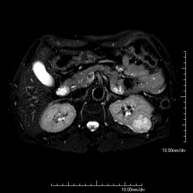

Prova diagnòstica no invasiva que consisteix en l'obtenció d'imatges d'alta definició anatòmica del fetge mitjançant l'ús d'un camp electromagnètic i ones de ràdio (amb un emissor i un receptor). No utilitza radiació ionitzant. Es realitza per estudiar qualsevol lesió localitzada en el fetge. Normalment es requereix l'ús de contrast paramagnètic (Gadolini) per caracteritzar les lesions. És necessari realitzat la prova en dejú (6 hores). - RM de Ronyons

Prova diagnòstica no invasiva que consisteix en l'obtenció d'imatges d'alta definició anatòmica d'ambdós ronyons mitjançant l'ús d'un camp electromagnètic i ones de ràdio (amb un emissor i un receptor). No utilitza radiació ionitzant. Es realitza per estudiar qualsevol lesió localitzada en ambdós ronyons. Normalment es requereix l'ús de contrast paramagnètic (Gadolini) per caracteritzar les lesions. - RM de Glàndules Suprarenals